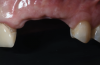

Fig 1. Frontal clinical view at baseline.

Figure 1

A systemically healthy 40-year-old male patient presented with a maxillary anterior vertical defect (Figure 1 and Figure 2). The patient stated that a previous bone grafting procedure was attempted in this area, but failed. The treatment plan involved a staged guided bone regeneration, the placement of three dental implants 9 months after bone augmentation, and soft-tissue grafting prior to implant loading to augment peri-implant soft-tissue thickness and keratinized mucosa width.